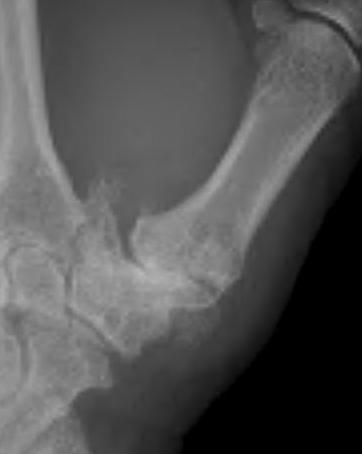

Eaton Classification

| Stage I | Stage II | Stage III | Stage IV |

|---|---|---|---|

|

Xray normal Synovitis |

Joint space narrowed Mild subluxation |

Severe joint space OA Radial subluxation of joint |

CMC + STT OA |